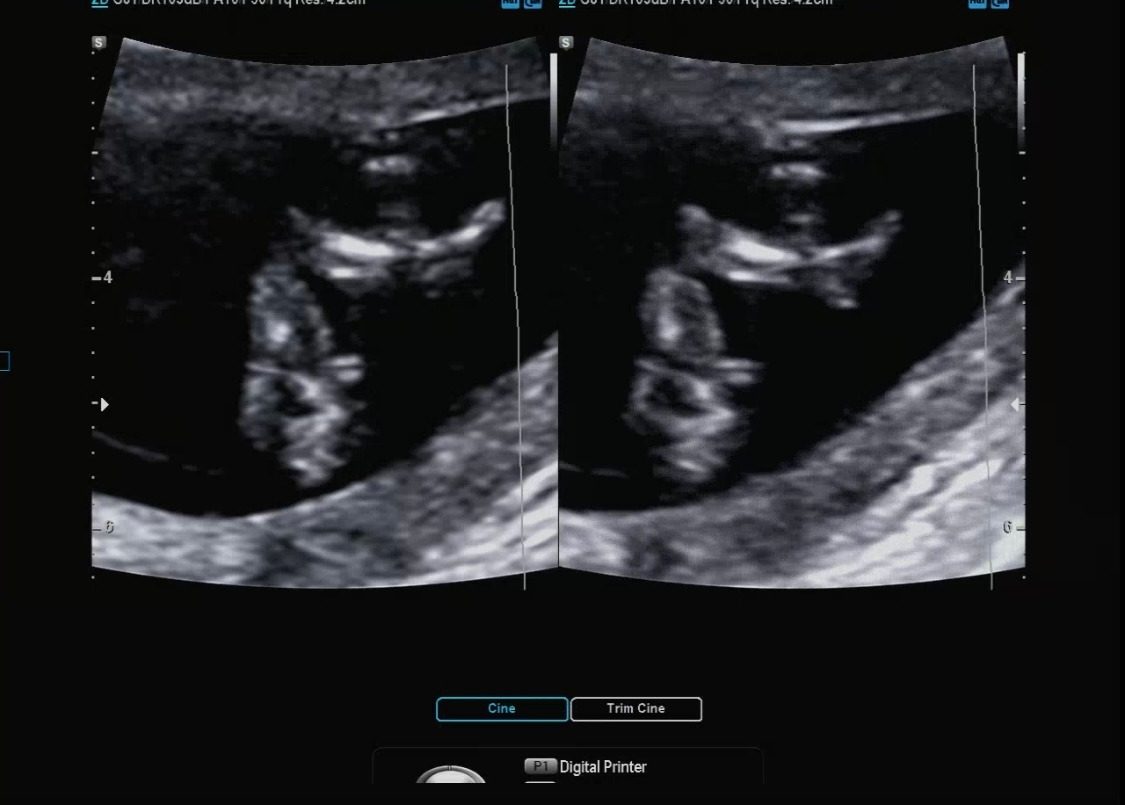

아가 사이즈 측정

머리에서 엉덩이까지의 길이

12주 차 3일 12주 차 4일이 나왔고, 원래 7일 정도의 차이는 존재한다고 알려주셨다.

사이즈는 6cm 정도로 컸더라 :)

딱 12주 차는 5.4의 자두 정도의 크기라고 베이비빌리를 통해 알고 있었다. 아마 12주 차 2일에 방문해서 아가가 조금 더 큰 거 같다. 하루하루 다르게 쑥 쑥 크고 있는 다올이의 모습이 참 신기하다.